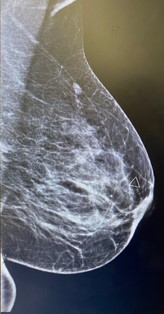

Figure 1: Left mammographic views ML of the left breast showing an irregular, spiculated, high-density mass in the upper outer quadrant. The lesion causes architectural distortion without associated calcifications. Findings are consistent with desmoid-type fibromatosis confirmed on histology.

Mammography presents irregular walled and highly dense lesion with no calcifications mimicking sometimes breast carcinoma [6].

Radiologic evaluation of our case revealed soft tissue mass inducing architectural distortion.